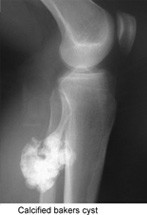

Calcified bakers cyst